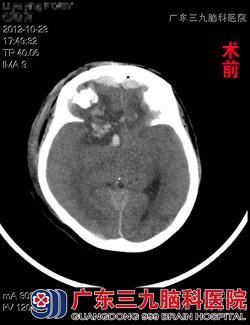

据了解,黎女士于2012年10月22日下午18时不幸发生车祸,当即出现不省人事,合并头部、口腔、鼻腔出血,呼叫无反应,被120急送当地医院救治,当地医院CT检查示:额骨粉碎性开放性骨折,右额叶挫裂伤并血肿形成,胸部DR示:创伤性湿肺;予以额部伤口填塞、压迫包扎止血,双侧鼻腔填塞纱条止血,气管插管保持呼吸道通畅,予以脱水、止血、补液等处理,治疗后黎女士病情无明显好转,意识状态进一步加重,为求进一步治疗而来到广东三九脑科医院。www.999brain.com

入院查体见黎女士呈深昏迷状态,可以自主呼吸,但呼吸稍深而快,颈软,双肺呼吸音粗,可闻及湿性罗音,四肢对刺痛无明显反应。头颅CT示:右侧额叶挫裂伤并血肿形成,前额跨中线硬膜外血肿,颅骨粉碎性骨折。完善术前检查,跟家属交待病情后,急诊在全麻下行冠切入路颅内血肿清除+双侧额颞顶去骨瓣减压术+气管切开术。术程顺利,术后回ICU继续治疗。术后5周,黎女士得以康复出院,出院时意识康复良好,四肢活动自如,可自行行走。www.999brain.com